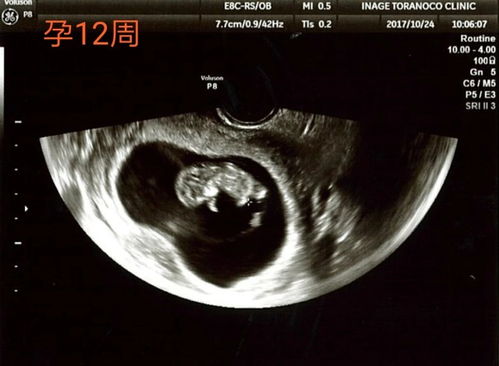

怀孕期间,定期进行产检是保障母婴健康的关键。其中,21周的系统B超检查是孕期中非常重要的一环。本文将为您详细介绍21周系统B超的重要性、检查内容以及注意事项。

1. 了解胎儿发育情况:21周的系统B超可以清晰地显示胎儿的各个器官、四肢、头部等部位,帮助医生判断胎儿的生长发育是否正常。

2. 排除胎儿畸形:通过系统B超,医生可以及时发现胎儿可能存在的畸形,如心脏、大脑、四肢等部位的异常。

3. 监测胎盘、羊水情况:系统B超可以观察胎盘的位置、厚度以及羊水的深度,评估胎儿在宫内的生长环境。

4. 评估胎儿体重:通过测量胎儿的头围、腹围、股骨长度等指标,可以初步判断胎儿的体重,为分娩做准备。